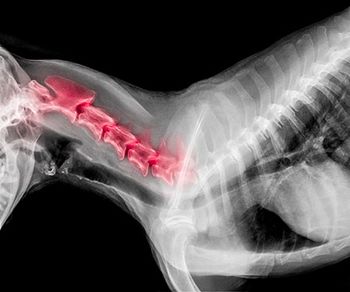

Recommendations for medical management of IVDD have changed, and corticosteroids are once again in the spotlight.

When used appropriately, steroids can play an integral role in the management of intervertebral disk disease.